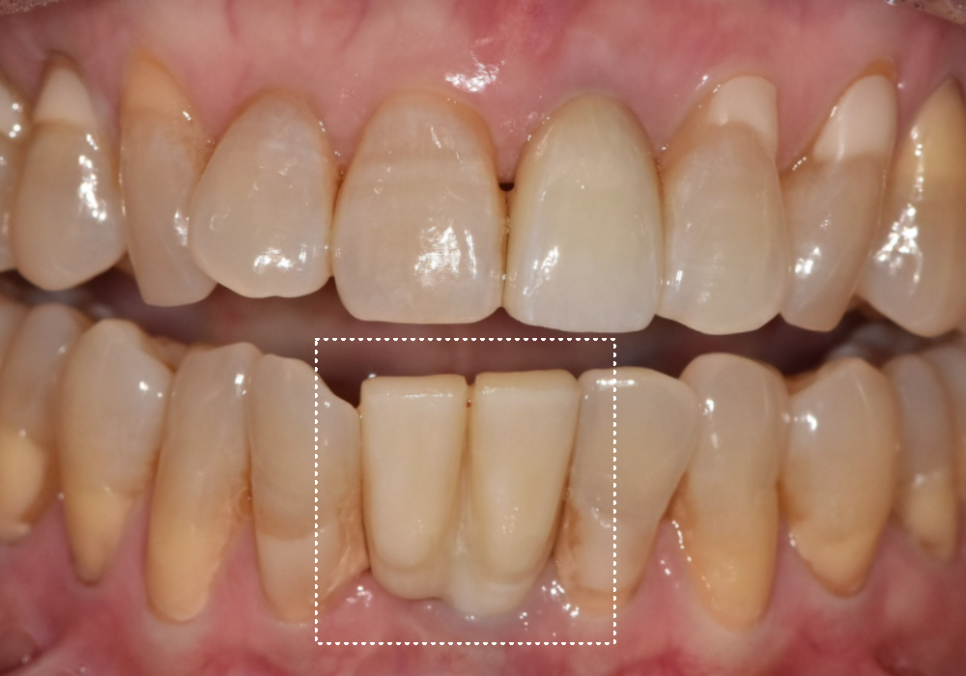

최종 완성된 모습입니다.

뿌리는 1개지만,

보철물은 2개가 들어갔습니다.

전혀 어색하지 않고

주변 치아와 자연스럽게 어우러지죠?

옆 치아의 길이와도 대칭을 이루어

심미적으로도 아주 만족스럽게 마무리되었습니다.